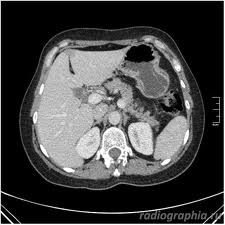

В начальной стадии ВИЧ: проводится изучение жалоб и анамнеза пациента, объективное обследование, анализы крови и мочи, рентгенография органов грудной клетки, микроскопическое исследование и посев мокроты на питательные среды, оценка внутрикожной реакции Манту. С учетом высокой частоты внелегочных поражений у ВИЧ-инфицированных больных туберкулезом, немаловажная роль в диагностике отводится биопсии лимфатических узлов, селезенки, печени, костного мозга и других органов. Проводится компьютерная томография. В качестве дополнительного исследования рекомендуется использование метода иммуноферментного анализа (ИФА) для выявления противотуберкулезных антител и антигенов.

Медицинские процедуры, проводимые при заболевании микобактериальная инфекция у вич-инфицированных больных: Клинический анализ крови, Общий анализ мочи, Биохимический анализ крови, Рентгенография грудной клетки, Посев мокроты с определеним чувствительности к антибиотикам (Мокрота в стерильный контейнер), Исследование мокроты, Реакция Манту, Биопсия лимфатических узлов, Биопсия костного мозга, Биопсия селезенки, Биопсия печени, Компьютерная томография, Иммуноферментный анализ